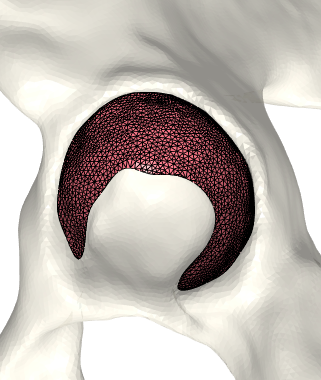

That is, we extrude each vertex 𝐯jsubscript𝐯𝑗\mathbf{v}_{j} in the direction of its normal by the displacement wjsubscript𝑤𝑗w_{j}. As a final step, we invert the bone-attached face normals before collecting the three disjoint sets of faces and vertices into a single mesh, (𝒱C,C)subscript𝒱𝐶subscript𝐶(\mathcal{V}_{C},\mathcal{F}_{C}). Observe in Fig. 3 the cartilage sub-surfaces combined into a single mesh.

Refer to caption

(a) Femoral cartilage.

(b) Femoral cartilage.

(c) Pelvic cartilage.

Figure 3: The final cartilage generated by our method for a femur (a), (b) and a pelvis (c). Notice how the cartilage aligns with the anatomical lines.